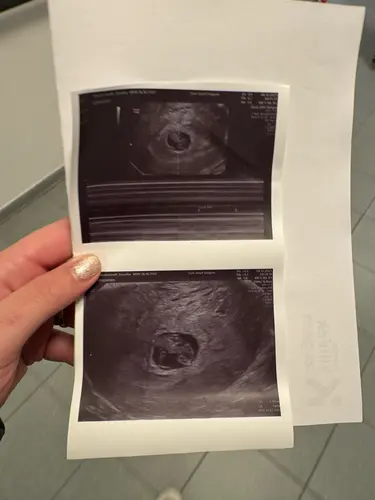

Ons baby'tje doet het goed. Zit mooi op de curve van groei, hartslag is 160 ondertussen. Gynaecoloog zei wel dat we een kleine vruchtzak hebben. Maar dat hij wel al iedere week mee gegroeid is dus dat het niet alarmerend zou zijn zegt ze. Ik moet gewoon wekelijks op controle wegens al eerdere miskramen en ze zei dat ze het goed ging opvolgen.

Ze stelde ons wel gerust dat je bij de ene gigantische ziet en bij de andere kleinere ze maakt haar niet echt zorgen omdat we al iedere keer een groei zagen.